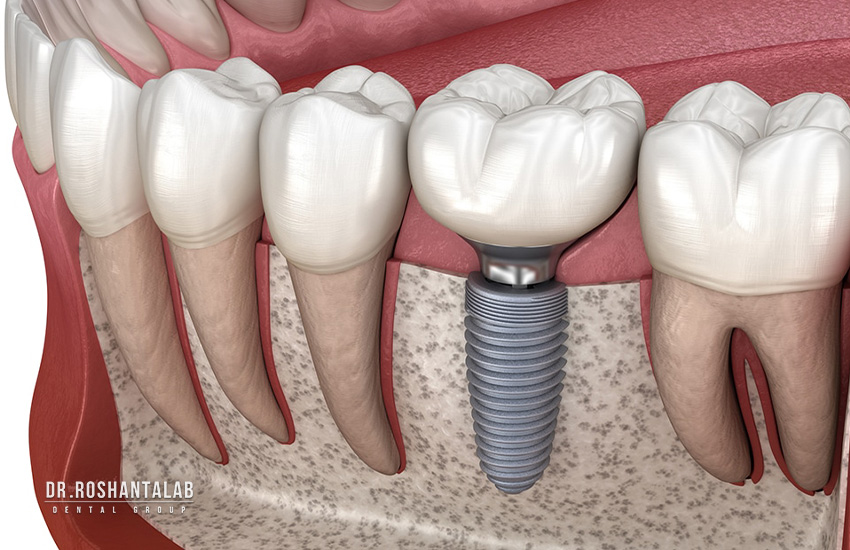

از دست دادن یک یا چند دندان، علاوه بر تاثیرات منفی بر زیبایی چهره و کاهش اعتمادبهنفس، عملکرد جویدن و تکلم را نیز با اختلال مواجه میکند. در میان تمام روشهای جایگزینی دندان، ایمپلنت دندان به عنوان تنهاترین راهکار دائمی و استاندارد طلایی شناخته میشود. اما یکی از بزرگترین موانع ذهنی بیماران برای شروع این درمان، یک سوال اساسی است: ایمپلنت دندان چقدر طول می کشد؟

زمان مورد نیاز: 3 تا 6 دقیقه برای هر دندان این مرحله، فاز اصلی جراحی است. جراح پس از اعمال بیحسی موضعی (یا در صورت درخواست بیمار، استفاده از روشهای سدیشن و بیهوشی در کلینیکهای مجهز مانند مراکز دکتر روشنطلب)، لثه را کمی کنار زده و با استفاده از دریلهای مخصوص دندانپزشکی، حفرهای با ابعاد دقیق در استخوان فک ایجاد میکند. سپس فیکسچر (پایه تیتانیومی ایمپلنت) با گشتاور مشخصی درون استخوان پیچ میشود. پس از آن، یک پیچ محافظ به نام کاور اسکرو (Cover Screw) روی ایمپلنت بسته شده و لثه روی آن بخیه میخورد.

زمان مورد نیاز: 3 تا 6 ماه (بخش اصلی زمان درمان) این مرحله در واقع پاسخی است به این که چرا ایمپلنت دندان چقدر طول می کشد. پایه ایمپلنت از جنس تیتانیوم خالص یا آلیاژهای آن ساخته شده است. تیتانیوم فلزی است که خاصیت “زیستسازگاری” (Biocompatibility) دارد؛ یعنی بدن آن را پس نمیزند، بلکه سلولهای استخوانساز (استئوبلاستها) به سمت آن حرکت کرده و روی سطح ایمپلنت استخوانسازی میکنند. این پدیده بیولوژیک بیومکانیکی که “اسئواینتگریشن” نام دارد، نیازمند زمان است. عجله در این مرحله و وارد کردن فشار زودرس به ایمپلنت، باعث شکست قطعی درمان (Fail شدن ایمپلنت) میشود. در این چند ماه، شما روکش ندارید (مگر در نواحی جلویی که از روکش موقت نمایشی استفاده میشود).

ایمپلنت دندان شبیه به پیچی است که باید در دیوار (استخوان) محکم شود. اگر استخوان فک شما در اثر کشیدن دندان در سالهای گذشته، عفونت، یا استفاده طولانیمدت از دندان مصنوعی تحلیل رفته باشد، قطر و ارتفاع کافی برای دربرگرفتن ایمپلنت را نخواهد داشت. در این حالت جراح مجبور است از پودر استخوان (آلوگرافت، زنوگرافت یا استخوان خود بیمار) برای بازسازی فک استفاده کند.